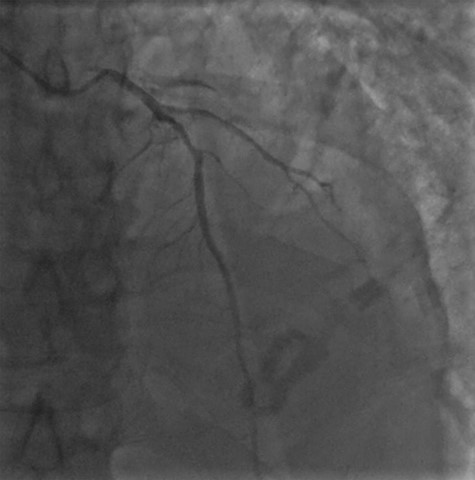

Cardiac MRI described a large aneurysm involving the basal and mid-inferoseptum and extending into the basal and mid-inferior walls (Fig. 2). There was full thickness infarction of the aneurysmal wall and an associated complex VSD with significant left to right flow (Qp:Qs 2.8:1). Coronary angiogram showed a mild circumflex disease and a significant disease of the left anterior descending (LAD) and right coronary artery (RCA) (Fig. 3).

Coronary angiogram demonstrating a diffuse coronary artery disease in the distribution of the left coronary artery.